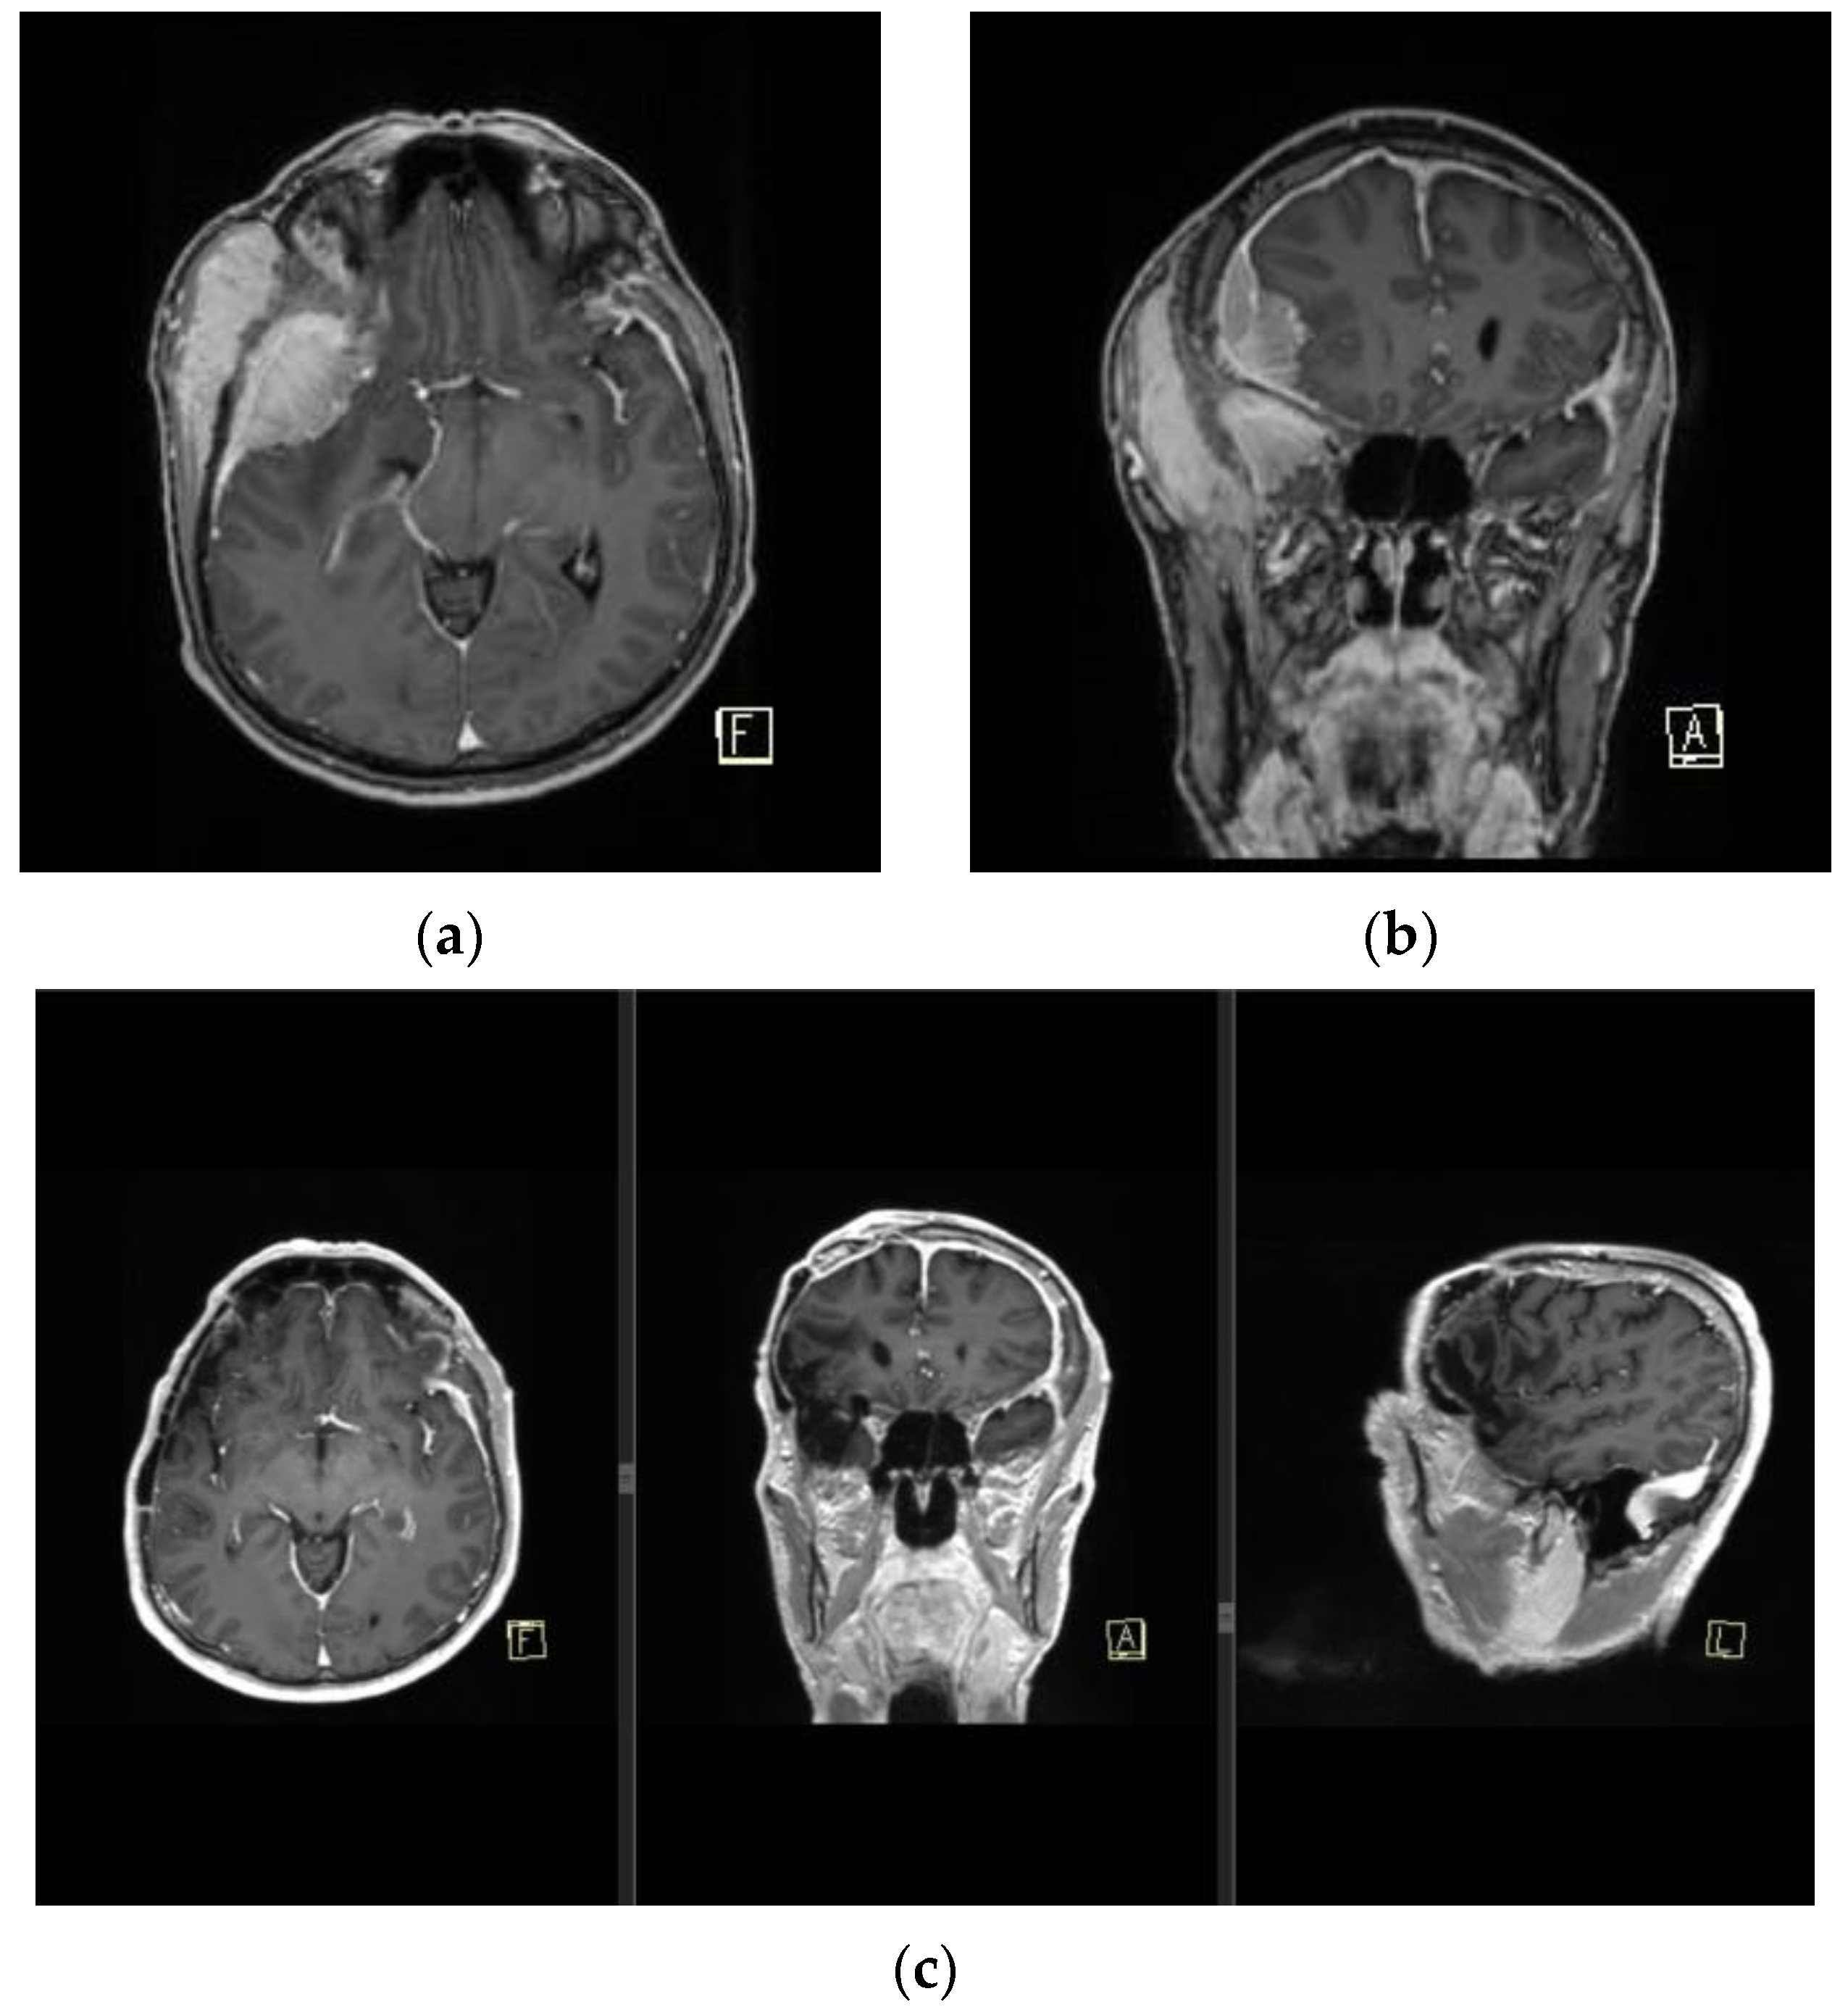

Anaplastic meningioma is the most commonly occurring histologic type of RIM, accounting for less than 5.0% of all meningiomas, with the worst prognosis (

Figure 5) [

27]. Radiation exposure has become one of the first theories regarding meningioma formation, along with early CNS trauma and hormone-induced/dependent meningioma formation [

28]. The prognostic factors in patients with anaplastic meningioma are unclear and remain controversial. Several retrospective studies have reported the importance of gross total resection (GTR) and its association with better survival outcomes. Nonetheless, a consensus in the literature has been achieved regarding the importance of adjuvant radiation regardless of the extent of resection [

29].